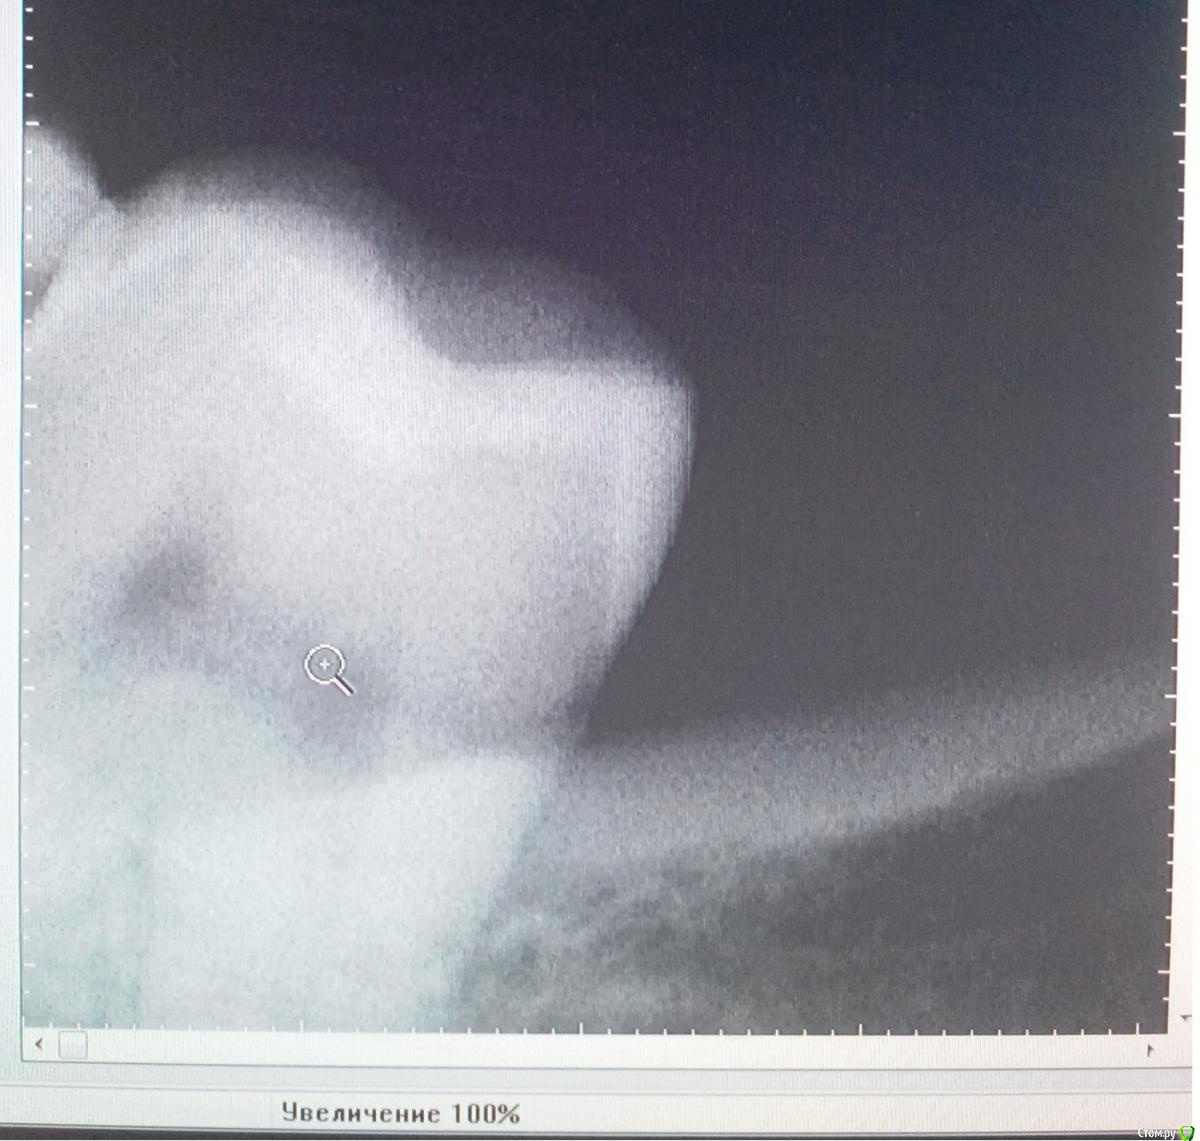

Дмитрий555 Опубликовано 3 февраля, 2016 Автор Поделиться Опубликовано 3 февраля, 2016 сходил в клинику, осмотрели. сделали снимок. Врач сказал, что на снимке ничего не увидел плохого: кость в норме, и остального ничего такого нет там. Похоже на то, что зуб верхней челюсти, после того как под ним удалили мой 38й нижний, лишился опоры, и стал давить на нижнюю десну. Верхний совсем плохой, его будем удалять. на рентгене - слева на снимке зуб, который на нижней челюсти слева самый дальний и крайний. Правее кость пошла челюсти. патологий получается нет там и никакие корни и зубы мудрости не прорастают? Ссылка на комментарий

shishok Опубликовано 3 февраля, 2016 Поделиться Опубликовано 3 февраля, 2016 Лучше бы панорамный снимок.На этом видно только коронку 7го и край альвеолярного отростка. 1 Ссылка на комментарий

IvanK Опубликовано 4 февраля, 2016 Поделиться Опубликовано 4 февраля, 2016 Лучше бы панорамный снимок.На этом видно только коронку 7го и край альвеолярного отростка.+1 по этому снимку можно сказать, что коронковая часть зуба есть Ссылка на комментарий